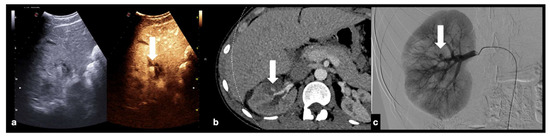

Active bleeding can be observed as micro-bubble extravasation outside blood vessels within the peritoneal or retroperitoneal space (Figure 17) [1,30].

Figure 17.

Follow-up CEUS of a 52−year-old blunt trauma patient with high-grade right kidney injury and extensive ischemia complication. Venous (a) phase CEUS examination shows multiple kidney lacerations with extensive ischemia complication and a small amount of perfused renal (caliper). At the same venous phase (b), CEUS active venous hemorrhage is well appreciated (arrow) confirmed at contrast-enhanced venous phase CT scan (c, arrow) and subsequent angiography (d).

- Contained vascular injuries:

Contained vascular injuries include pseudoaneurysms and arteriovenous fistulas. Pseudoaneurysms are focal outpouchings of the external vessel contour due to the partial disruption of the wall, which is contained by the tissue around the vessel (Figure 18, Figure 19 and Figure 20) [1,30].

Figure 20.

CEUS (a) of a 23−year-old man referring to the emergency department for direct blunt trauma to the right flank showed the presence of a small pseudoaneurysm (white arrow) inside the contusion area of the right kidney; the diagnosis was then confirmed at the axial arterial phase contrast-enhanced CT scan (b), as well as at angiography performed for treatment purposes (c).